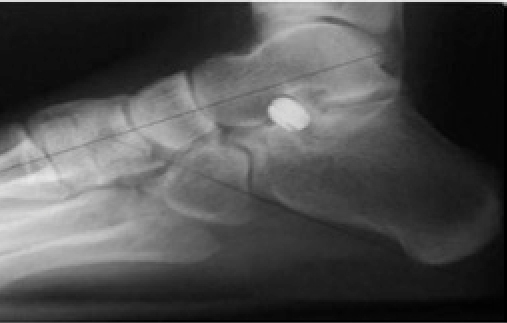

- To treat the hindfoot’s overpronation, the surgeon raises the talus head up and backward. After making an incision in the tarsal sinus, a guidewire is placed in the general direction of the tunnel.

The suture is usually removed 12-14 days following the procedure. Three weeks after surgery, non-weight-bearing workouts like swimming and biking are typically advised. Six weeks following surgery, partial weight-bearing functional exercises are recommended. After 12 weeks, an X-ray must be done every three months to monitor the deformity’s repair and the implant’s position.